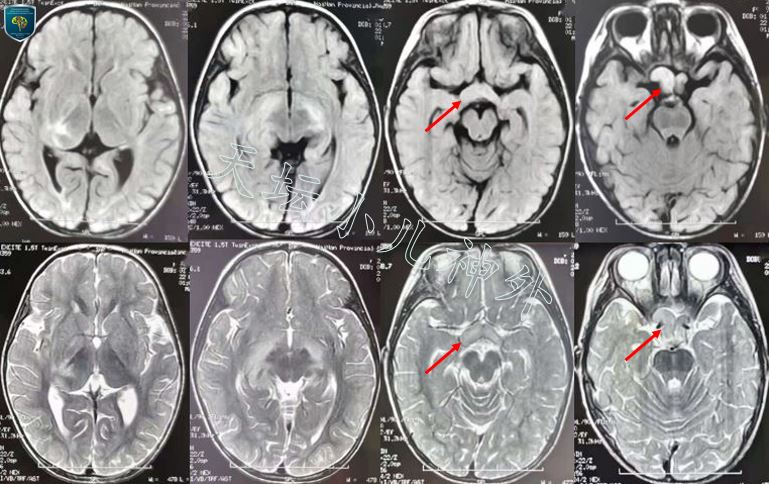

图1.患儿三年前(22月龄)时头部MRI平扫显示右侧视神经、视束增粗(红色箭头),右侧丘脑旁不规则信号影,考虑视路胶质瘤可能性大,未予治疗。

图2.本次入院前检查(5岁龄)肿瘤明显进展,头颅CT示右侧视神经、视交叉、下丘脑及右侧丘脑枕可见不规则低密度影,边缘条状钙化;MRI示视交叉、下丘脑及右侧丘脑枕可见不规则长T1长T2信号影,边缘欠清,不均匀强化,视路胶质瘤可能性大。